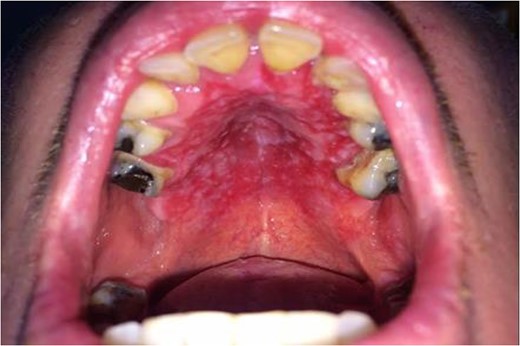

A healthy 42-year-old postman presented to his dentist complaining of a 6-month history of itching and discomfort in the maxillary gingivae. After unsuccessful treatment for oral candidiasis, he was provisionally diagnosed with erosive lichen planus and referred to the local maxillofacial department. At initial clinical presentation at the maxillofacial unit, the patient was observed to have florid erythroleukoplakia of the hard palate and buccal gingivae (Fig. 1). All maxillary teeth were found to mobile. There were no cutaneous lesions. A social history revealed a 25-year pack-history of cigarette smoking. The patient admitted to drinking up to eight cans of cider per day.